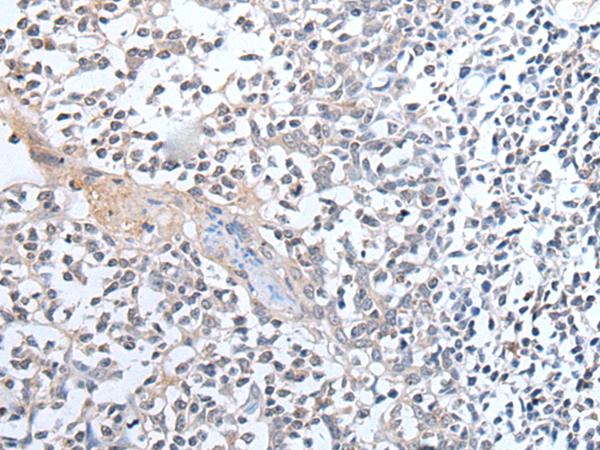

分类: 科研抗体货号: P12808别名: OX; PPOX; NRCLP1应用: IHC反应种属: Human, Mouse, Rat